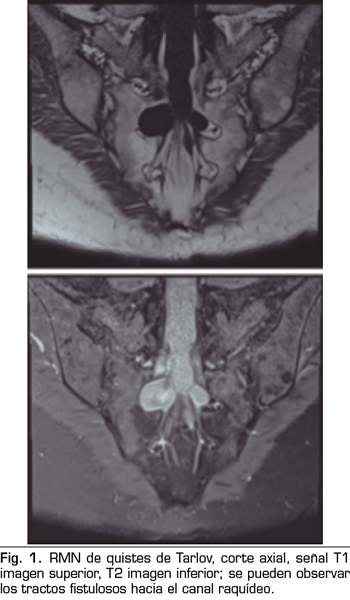

Se realiza una RMN donde no se observan alteraciones estructurales que justifiquen las dolencias que presenta. Como hallazgo casual se describen quistes de Tarlov a nivel de S2. Se solicita una valoración por el servicio de neurocirugía, quienes dudan que la clínica sea consecuencia de los quistes (Figuras 1 y 2).

Una de las causas de dolor crónico a tener en cuenta son los “quistes perineurales” o “quistes de Tarlov”. Desde su primera descripción en 1938, son numerosos los artículos en los que se hace referencia. Se trata de lesiones nerviosas que se producen más frecuentemente en la zona sacra (8). En un estudio de Paulsen RD sobre la prevalencia y el drenaje de los quistes de Tarlov, se observó que en 500 pacientes que se sometían a una Resonancia Magnética (RMN) por dolor lumbar, el 5 % presentaba quistes de Tarlov y un 20 % de esos pacientes padecían síntomas relacionados con ellos (9,10). El diagnóstico suele ser casual mediante RMN; la cifra es variable debido a que solo se solicita a aquellos pacientes que presentan dolor lumbar crónico. Dicha técnica es más sensible que la tomografía axial computerizada (11,12).

Los “quistes perineurales” o “Quistes de Tarlov” son alteraciones en la duramadre de las raíces nerviosas, que se producen más frecuentemente en la zona sacra. El diagnóstico suele ser casual mediante RMN; la incidencia es variable, debido a que el hallazgo es incidental. Habitualmente son asintomáticos, pero pueden producir radiculopatía, dolor perineal o vejiga neurógena, entre otros.